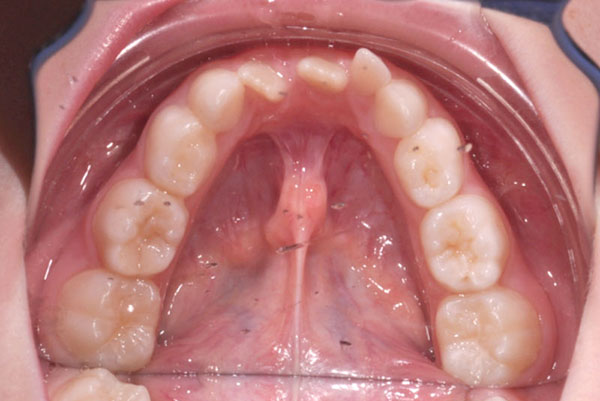

Overjet aumentato con incisivi superiori molto sporgenti (così detto aspetto del Brutto anatroccolo)

Il trattamento ortodontico nel bambino con “denti sporgenti” consente, ottimizzando il tempo di utilizzo delle apparecchiature, di ridurre il rischio di frattura traumatica dei denti anteriori, di migliorare l’estetica e di aumentare l’autostima del paziente (riducendo le conseguenze del bullismo di coetanei tipico di queste condizioni).